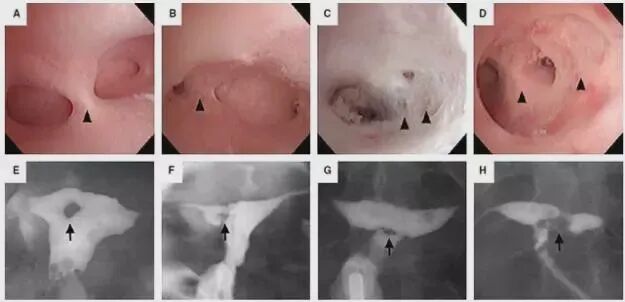

宫腔镜主要适用于子宫内膜薄、内膜形态异常、反复移植失败、造影及其他影像检查怀疑子宫畸形或异常发现、反复流产、阴道出血等疾病及输卵管通畅性检查等等。

曾有专家总结了1000 例IVF 前常规宫腔镜检查结果,提示宫腔正常者占62%, 子宫内膜息肉者占32%,黏膜下肌瘤和宫腔粘连者各占3% 。

而在进行宫腔镜检查治疗的过程中,子宫内膜受膨宫液的冲刷,宫腔均匀、机械性地扩张可能使内膜某些基因表达发生短时改变,促进内膜释放出有利于胚胎种植的生长因子和细胞因子,从而有利于胚胎着床,提高妊娠率。

大多是由于各项辅助检查提示有异常,比如:多次B超提示内膜增长过厚,内膜形态异常,宫腔粘连,内膜不光整等等,输卵管造影提示宫腔有粘连,形态不规则等。

(1)对于多次移植(≥2次)失败的患者,宫腔镜检查可以排除由于子宫因素造成的不着床;

(2)多次流产史(≥3次)或者流产后月经有明显改变的患者,宫腔镜检查可以排查宫腔粘连等问题并且根据情况进行治疗。

(3)对于部分胚胎很宝贵的患者,比如说多次促排卵只有2、3个胚胎,或者做三代试管婴儿的患者,由于胚胎来之不易,那么在移植前进行宫腔镜检查也是为了移植的成功做准备。

(4)促排周期内B超多次提示宫腔有异常,那么在准备移植之前我们也有必要做一下宫腔镜检查;

(5)既往剖宫产的试管婴儿女性们,若多次B超提示宫腔分离,那么宫腔镜检查不但可以观察是否存在剖宫产憩室,还能测量憩室大小,制定相应的治疗方案。